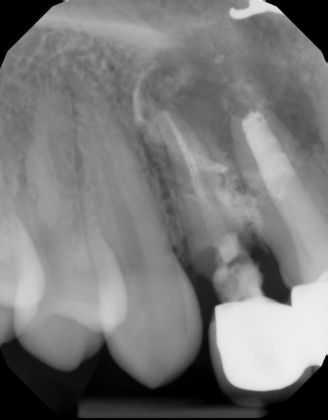

Two implants with crowns replacing infected root canals and old porcelain fused to metal crowns